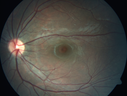

Congenital hypertrophy of the retinal pigment epithelium CHRPE703 viewsFAF, Optos Photo and FAJun 11, 2019

Congenital hypertrophy of the retinal pigment epithelium CHRPE443 viewsJun 11, 2019

Congenital hypertrophy of the retinal pigment epithelium CHRPE462 viewsFA was done for scleritis in the fellow eyeJun 11, 2019